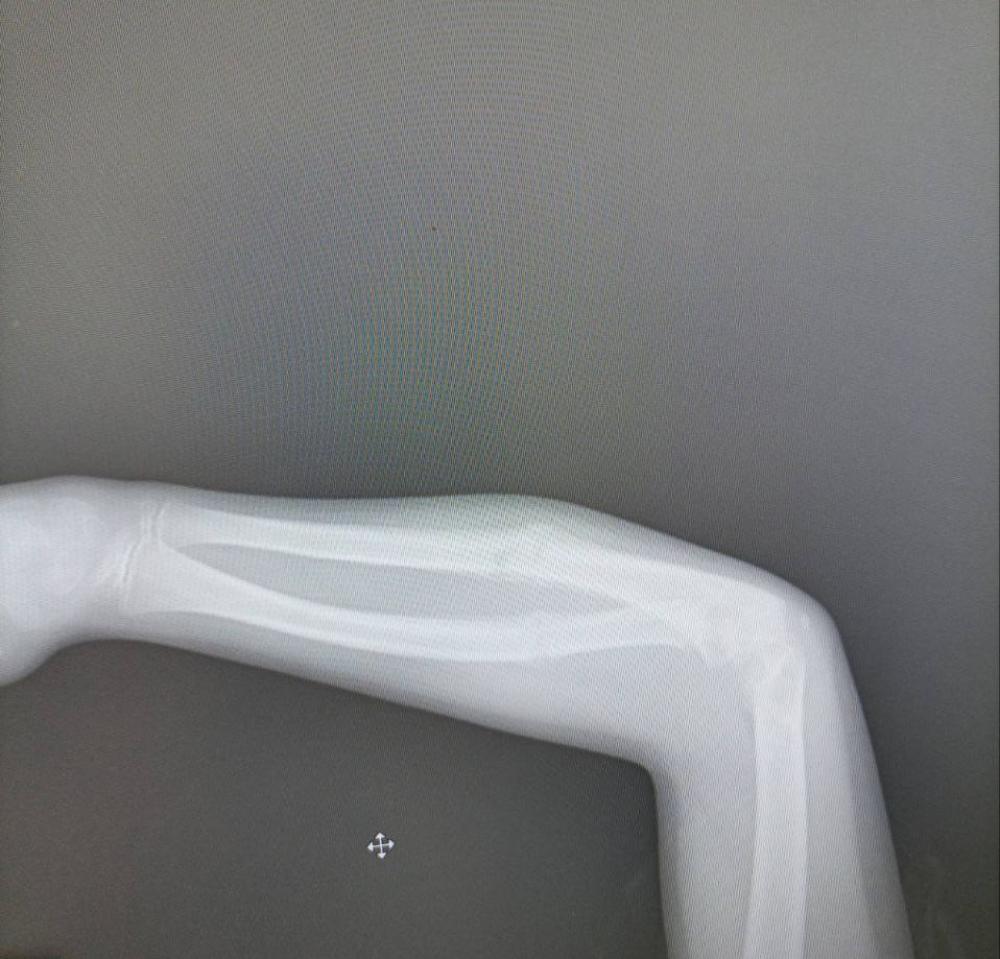

У Рівненській обласній дитячій лікарні прооперували дитину із викривленням кісток правого передпліччя.

Як з’ясувалося із розмови з пацієнтом та його мамо, така проблема з’явилась після перелому кісток передпліччя у липні 2022 року. Пацієнт лікувався за місцем проживання, проте за місяць у гіпсовій пов’язці кістки змістились та неправильно зрослись.